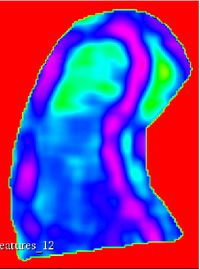

Texture feature maps

Run Length texture feature maps